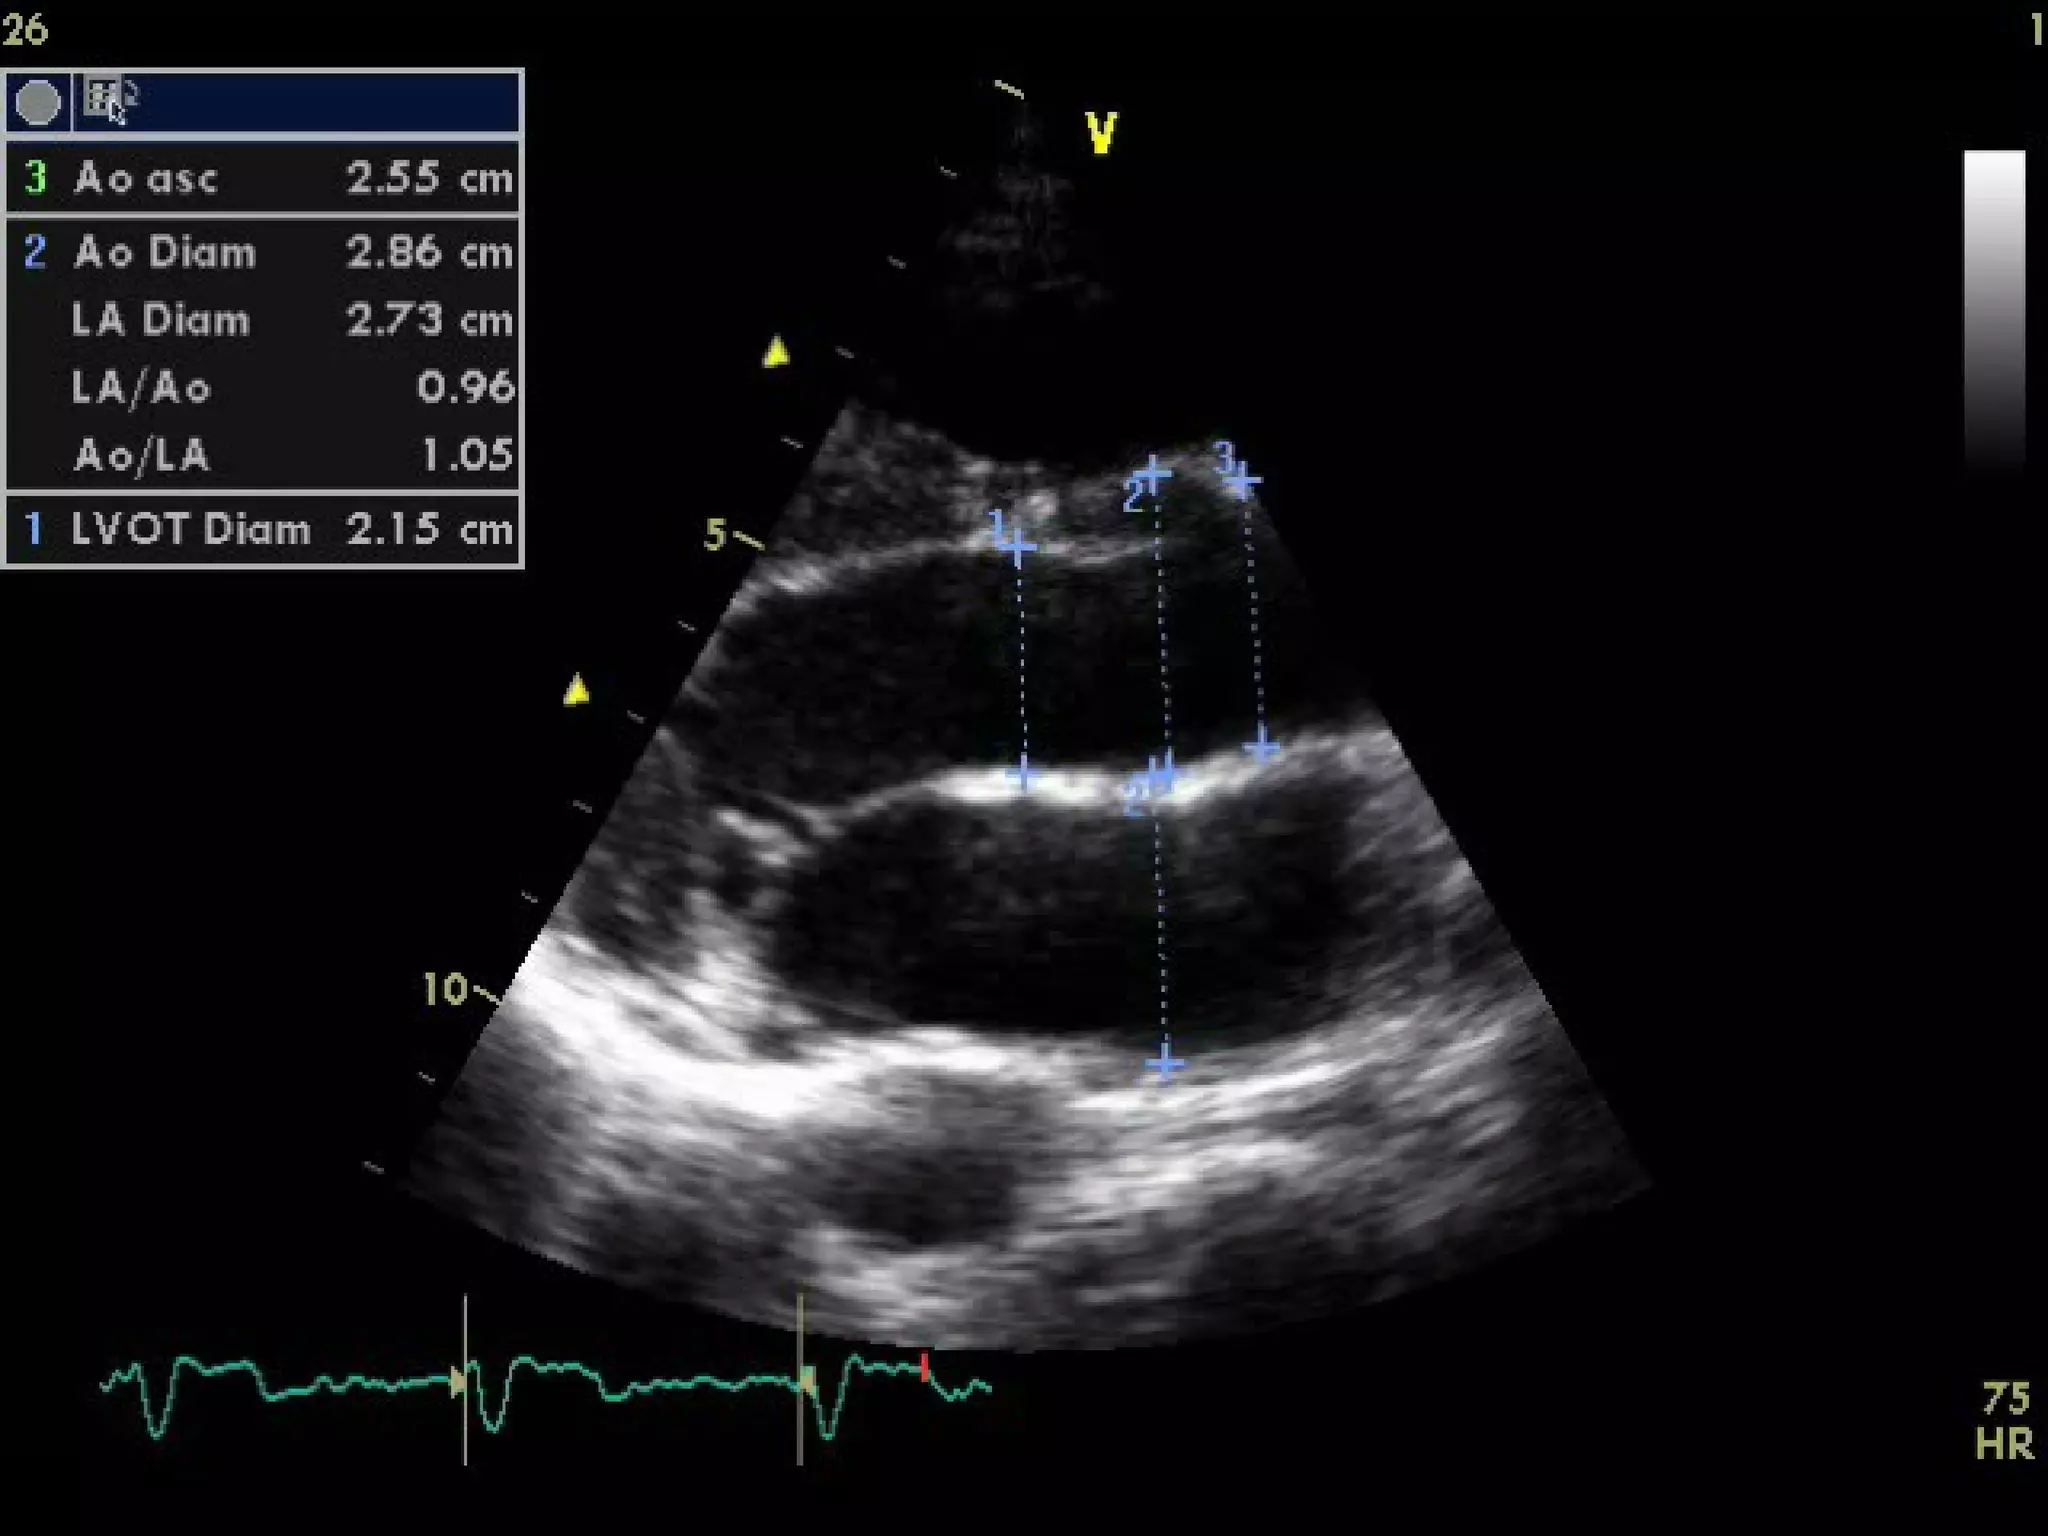

Parasternal long axis

With the transducer in the 3rd or 4th right intercostal

space immediately adjacent to the sternum and

patient in left lateral decubitus a long-axis view of

the heart is obtained which bisects the aortic and

mitral valve, Proper positioning of the probe results

in the ascending aorta being relatively horizontal in

orientation.

Parasternal long axis Withthe transducer in the 3rd or 4th right intercostal space immediately adjacent to the sternum and patient in left lateral decubitus a long-axis view of the heart is obtained which bisects the aortic and mitral valve, Proper positioning of the probe results in the ascending aorta being relatively horizontal in orientation. Lower intercostal positions may be necessary in patients with vertically oriented hearts due to chronic obstructive pulmonary disease.